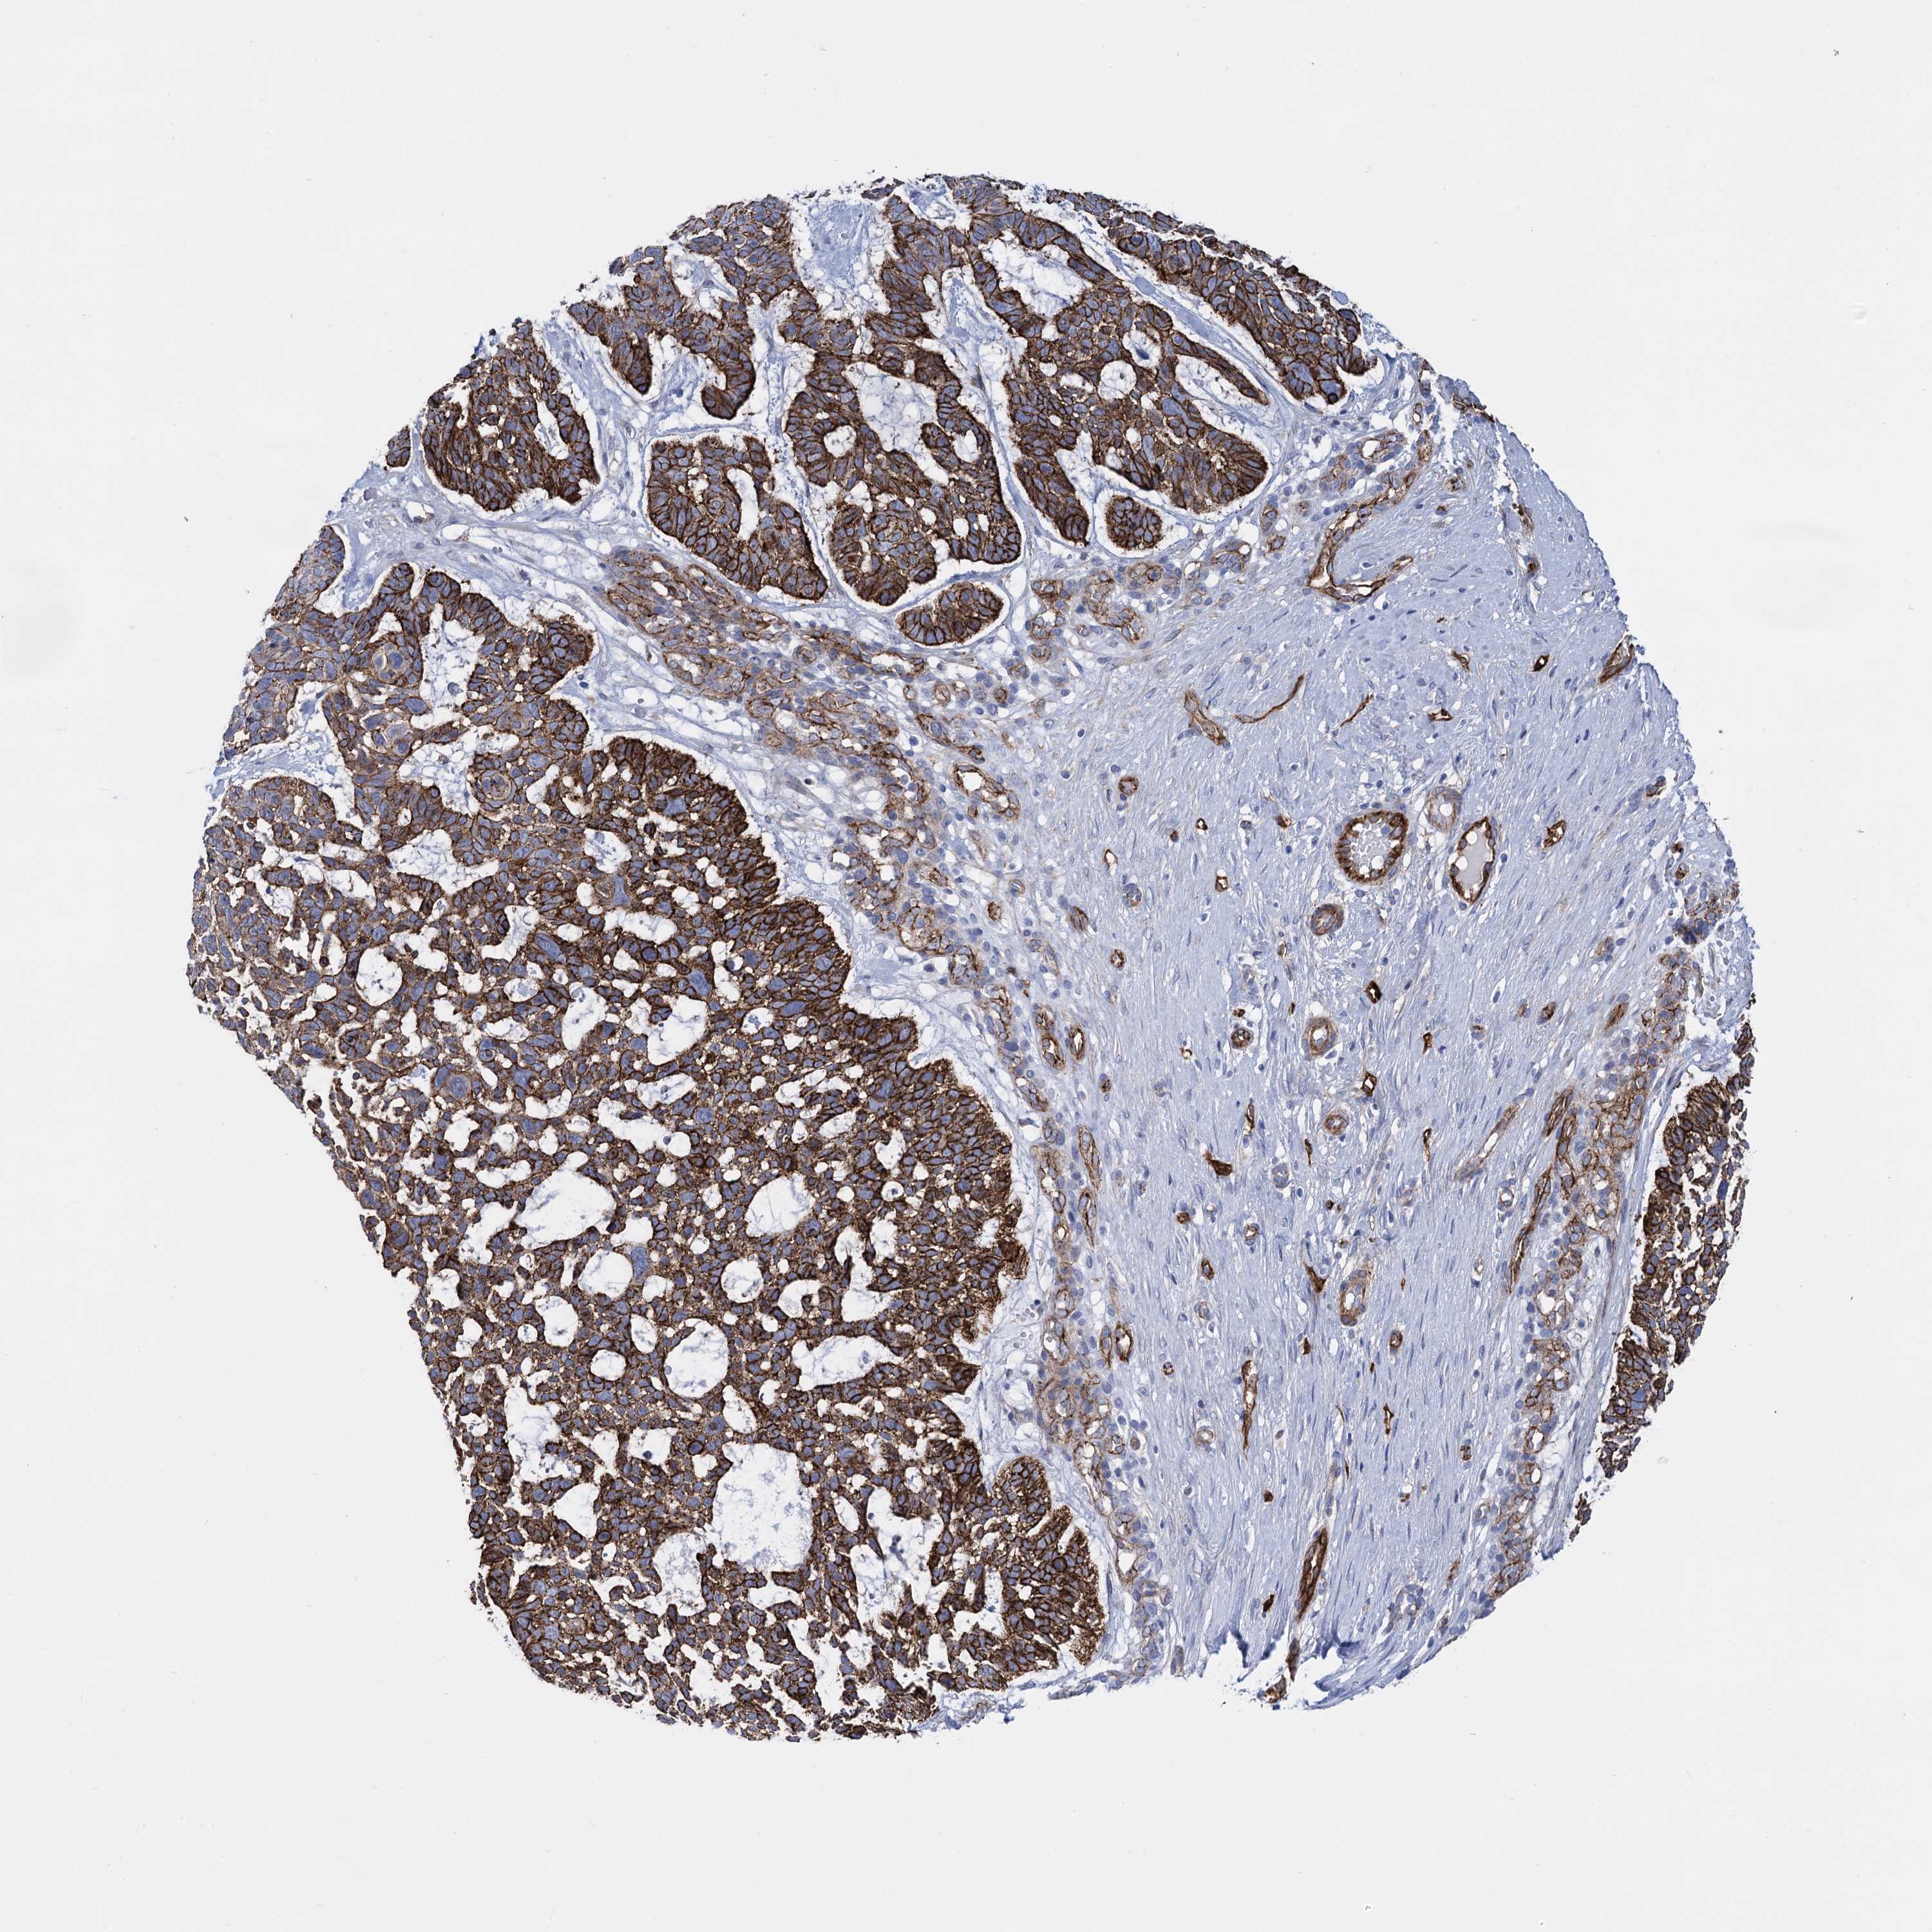

SKIN CANCER - Protein expressioni

A mouse-over function shows sample information and annotation data. Click on an image to view it in a full screen mode. Samples can be filtered based on level of antibody staining by selecting one or several of the following categories: high, medium, low and not detected. The assay and annotation is described here.

Antibody stainingi

Antibody staining in the annotated cell types in the current human tissue is reported as not detected, low, medium, or high, based on conventional immunohistochemistry profiling in selected tissues. This score is based on the combination of the staining intensity and fraction of stained cells.

Each image is clickable and will lead to virtual microscopy that enables deeper exploration of all samples and also displays staining intensity scores, fraction scores and subcellular localization as well as patient and tissue information for each sample.

Antibody HPA014404

Antibody CAB001452

Antibody CAB040581

Antibody CAB080022

Staining

High

Medium

Low

Not detected

Intensity

Strong

Moderate

Weak

Negative

Quantity

>75%

75%-25%

<25%

None

Location

Nuclear

Cytoplasmic/membranous

Cytoplasmic/membranous,nuclear

Squamous cell carcinoma, NOS

Basal cell carcinoma

Adnexal tumor, benign

Squamous cell carcinoma, metastatic, NOS